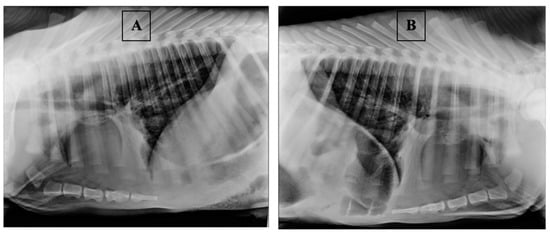

- Farrow, C.S. Bovine pneumonia. Its radiographic appearance. Vet. Clin. N. Am. Food Anim. Pract. 1999, 15, 301–358. [Google Scholar] [CrossRef]

- Fowler, J.; Stieger-Vanegas, S.M.; Vanegas, J.A.; Bobe, G.; Poulsen, K.P. Comparison of Thoracic Radiography and Computed Tomography in Calves with Naturally Occurring Respiratory Disease. Front. Vet. Sci. 2017, 4, 101. [Google Scholar] [CrossRef] [PubMed]